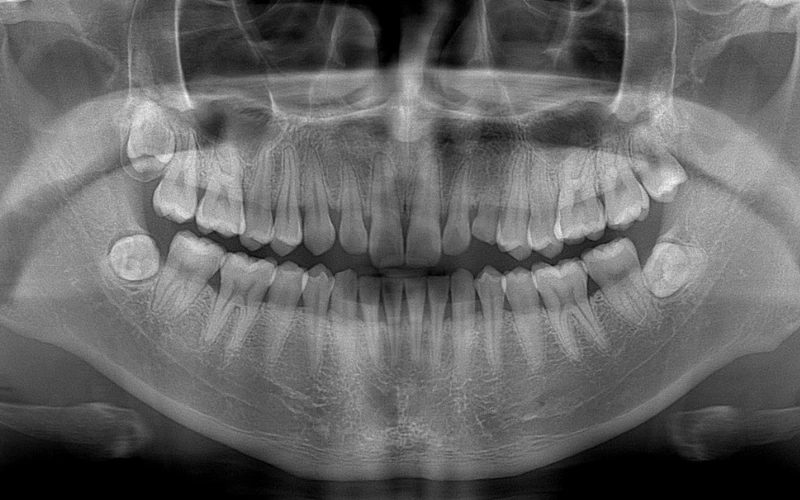

Chất lượng hình ảnh

Công nghệ chụp tự động kỹ thuật số đặc biệt áp dụng tự điều chỉnh thang xám nhằm hạn chế tối đa sai sót, khiến chất lượng hình ảnh cực kỳ rõ ràng và sắc nét.